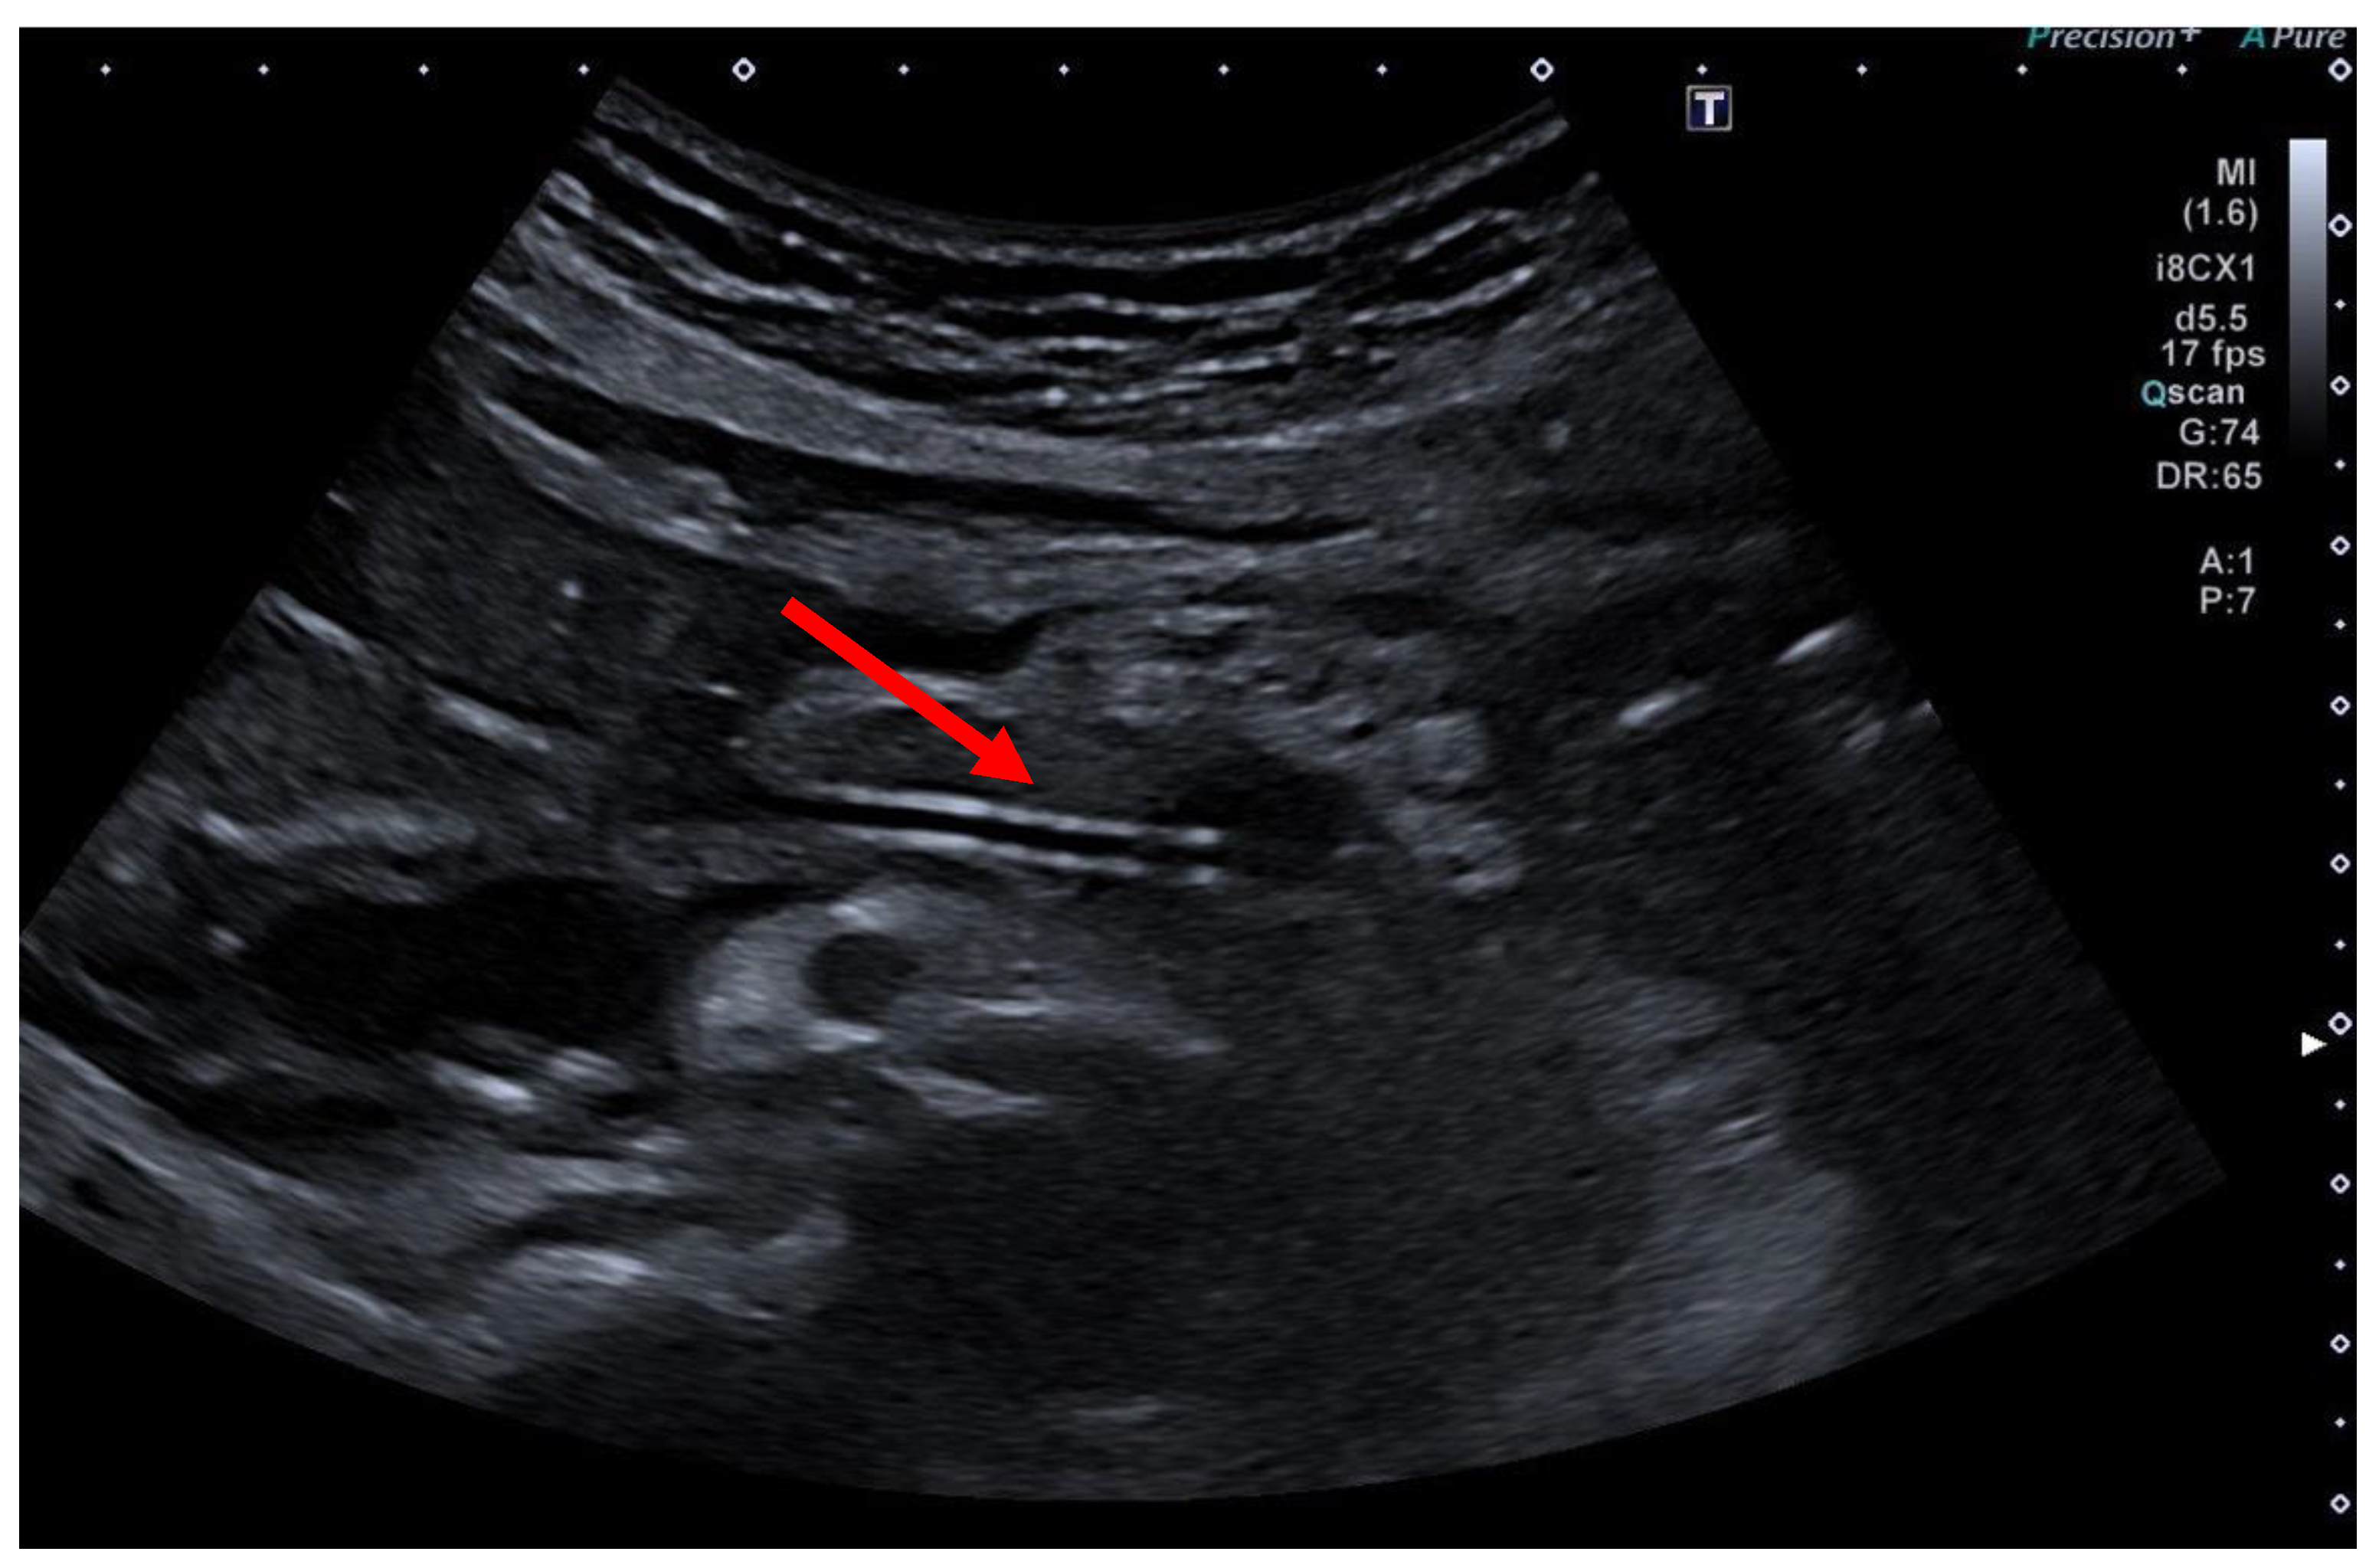

A transabdominal ultrasound examination on the first post-interventional day is essential to monitor successful treatment. A decrease in the diameter of the pancreatic duct compared to previous observations and the detection of air within the duct are signs of an effective drainage (Figure 10).

From a very practical point of view, the vast majority of institutions routinely image patients after a EUS-PD utilizing CT. This might be due to usual rather limited expertise in wide-spread use of transabdominal ultrasound for various purposes and a lack of advanced sonographers. However, as the authors stated, a transabdominal ultrasound is the preferred diagnostic tool of choice for post-procedure imaging, easily revealing “a decompressed pancreatic duct with transgastric plastic stent in place (red arrow)” as expressed in the legend of Figure 10.

Figure 10. Postinterventional ultrasound control after EUS-PD revealing a decompressed pancreatic duct with a transgastric plastic stent in place (red arrow), selected from the clinical picture library of the reporting Dept. of Gastroenterology, Hepatology and General Internal Medicine.